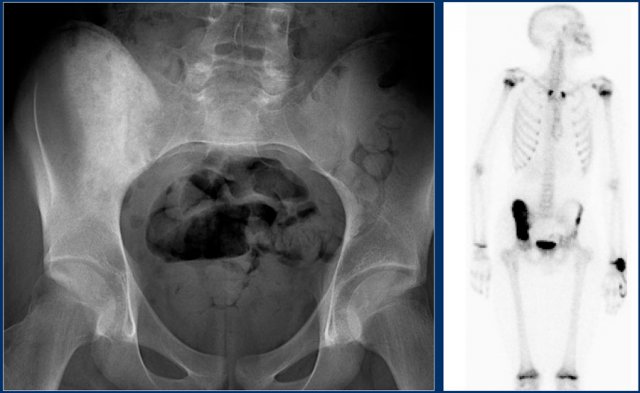

Here another young patient with an osteosarcoma.

There is homogeneous sclerosis of a large part of the right hemipelvis with intense uptake on the bone scintigraphy.